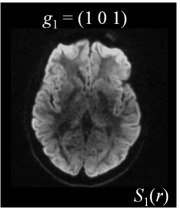

Six axial DW measurements and one non-DW image are shown in Figure 1, along with the corresponding magnetic field gradients . Note the difference in intensity values for different gradient directions.

| (a) | (b) | (c) | (d) |

| (e) | (f) | (g) | (h) |